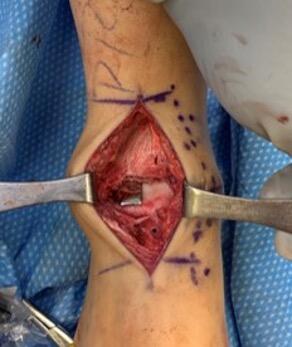

The incision was the typical anterior ankle approach. This would limit location of incisions for potential future issues or conversion to fusion or total implant. We then exposed the distal tibia and dorsal neck of the talus. Placing the prefabricated custom cut guide onto the neck of the talus, we then checked this under fluoroscopy to ensure placement, and the proper orientation and amount of lateral dome to be removed. We then pinned this guide in place with predetermined holes. A reciprocating blade limited blade excursion and minimized potential for injury to adjacent structures. After removal of the damaged piece of talus we placed the trials. The goal was to have the trial flush or even slightly recessed with regard to the adjacent cartilage. During weight bearing, the native cartilage will compress, so it is important to match the weight bearing level. If the implant is proud, then during weight bearing the cartilage will naturally compress, but the implant will not, potentially giving rise to issues with load bearing around the device.

After appropriate sizing, the guide allowed creation of holes for the final implant stems. After implant placement we performed range of motion followed by layered closure and application of a posterior splint. She was kept non-weight bearing for three weeks and once the skin healed, progressed to weight bearing as tolerated. To date, one year later, there have been no issues and she has returned to work.